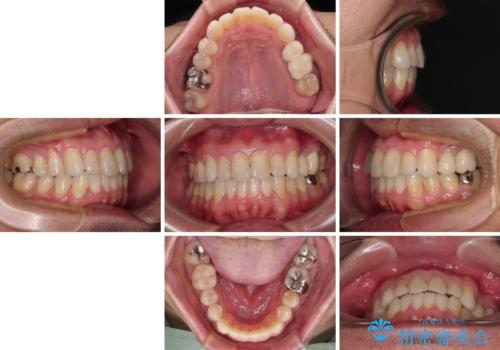

内側に転位した歯とボロボロのむし歯 インビザラインによる矯正治療とむし歯治療

ボロボロとなっていた歯は抜歯が必要な状態でしたが、舌側転位している歯を移動させることで抜歯スペースを埋めることができるため、矯正治療により歯列を整えることとしました。

舌側転位の改善にインビザラインを用いるのはやや難易度が高くなりますが、前歯部のデコボコは軽度であったため、インビザラインによる矯正治療を行うこととしました。

矯正治療後には抜歯が必要な歯に隣接してむし歯となっていた歯をオールセラミッククラウンにて補綴治療を行うこととしました。

矯正治療開始時に、インビザライン矯正の加速装置を購入されましたが、インビザライン自体をあまりしっかりと使用できず、4年間の治療期間となりました。